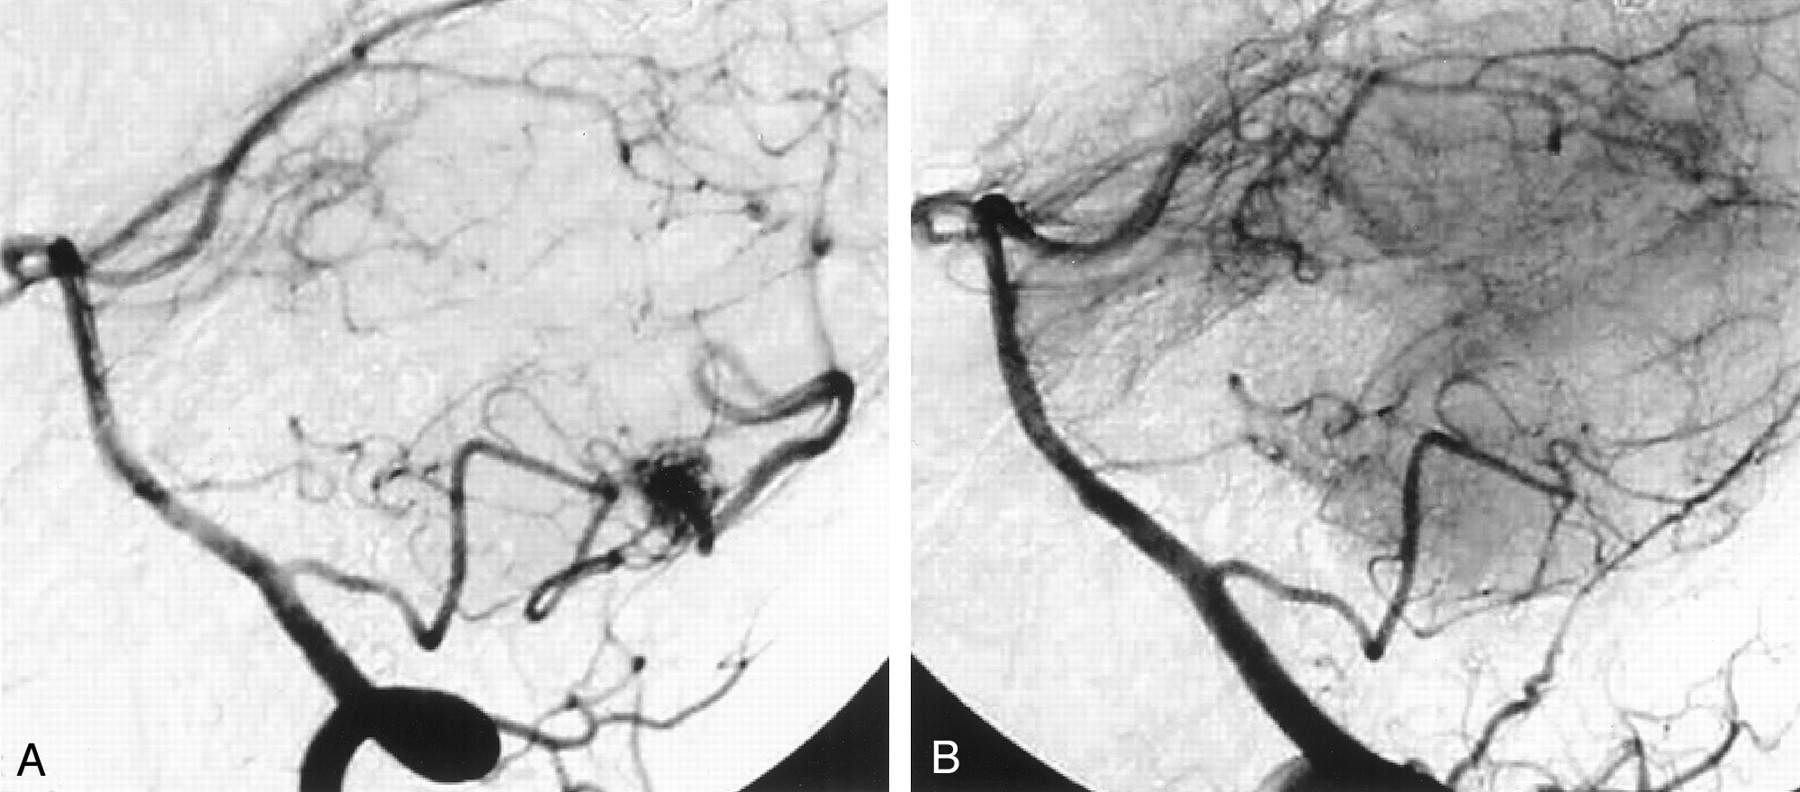

The research and work followed the treatment of tangled blood vessels in the brain, or arteriovenous malformations, through an embolisation procedure performed by the Neuroradiology team at Western General Hospital’s Department of Clinical Neuroscience. In this process, a glue-like substance is introduced into the brain which changes the smell of the breaths of both neuroradiologist and patient. As there is no “opening-up” of the body, the procedure leaves no visible scars and this so-called “Onyx smell”, which lingers in the wards after the intervention, is the only physical indicator of the operation that took place.